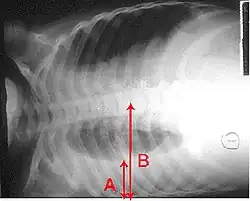

Pro stanovení diagnózy se často používá rentgenový snímek hrudníku.[10] U osob s mírnými projevy onemocnění je snímkování potřebné pouze u osob s potenciálními komplikacemi, u pacientů, jejichž stav se ani při léčbě nelepší, nebo u těch, u nichž je příčina onemocnění nejasná.[10][37] Pokud je stav nemocného natolik vážný, že je nezbytná hospitalizace, doporučuje se provést rentgen hrudníku.[37] Nález však ne vždy odpovídá závažnosti onemocnění a ne vždy spolehlivě rozliší mezi bakteriální a virovou infekcí.[10]

Rentgenové snímky zápalu plic lze klasifikovat jako lobární pneumonii, bronchopneumonii (rovněž známou jako lalůčkový zápal plic) a intersticiální pneumonii.[40] Bakteriální, komunitně získaná pneumonie klasicky vykazuje známky plicní konsolidace jednoho segmentálního plicního laloku, tedy znaky lobární pneumonie.[20] Nálezy se však mohou lišit, a u dalších typů zápalu plic jsou běžné jiné charakteristiky.[20] Aspirační pneumonie může vykazovat oboustranné zastínění zejména ve spodní části plic a na pravé straně.[20] Rentgenové snímky virového zápalu plic se mohou jevit normální, vykazovat hyperinflaci, ostrůvkovité oblasti konsolidace plicní tkáně na obou plicích nebo se podobat bakteriálnímu zápalu plic s lobární konsolidací.[20] V raných fázích onemocnění nemusí být radiologické nálezy patrné, zvláště při dehydrataci, nebo může být obtížné je interpretovat u obézních osob nebo těch, kteří již onemocnění plic prodělali.[11] Počítačová tomografie může u nejasných příčin poskytnout další informace.[20]